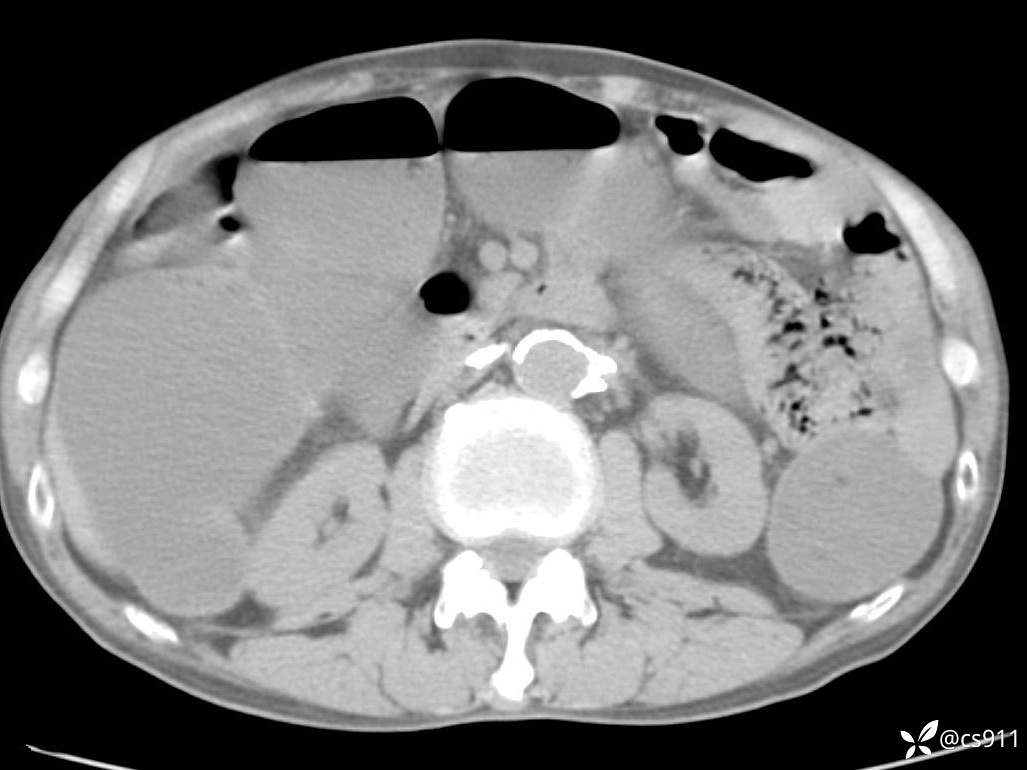

急腹症之急诊CT,原因?答案公布

男,77岁,腹痛、腹胀伴恶心呕吐1天。呕吐胃内容物,非喷射性呕吐,有咖啡色样胃内容物,诉有胃穿孔病史。查体:全腹平,下腹部压痛,全腹无反跳痛,叩诊呈浊音,移动性浊音阴性,肠鸣音减弱,1-2次/分。肛检:直肠未扪及明显肿物,可触及大量粪块。

血淀粉酶(AMY) HH 1859 U/L 35-135

癌胚抗原(CEA) H 27.44 ng/ml 0-5